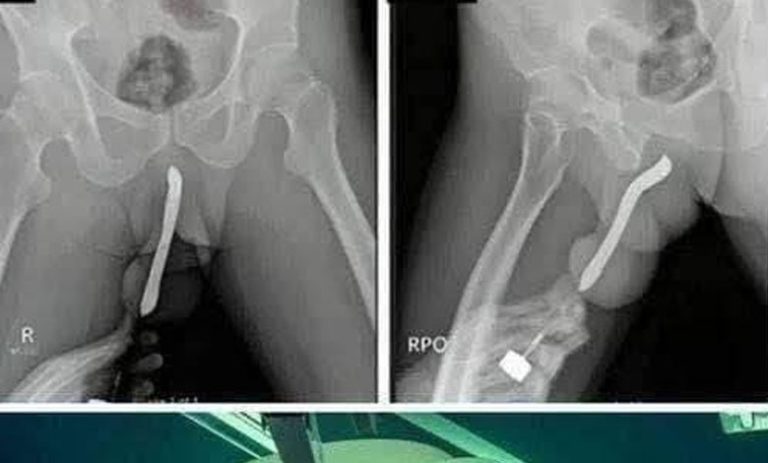

According to initial reports, the teenager had been alone in her room when the incident occurred. It is believed that the act may have been driven by curiosity, misinformation, or a lack of proper sexual education. Unfortunately, the consequences were far more serious than she expected. The